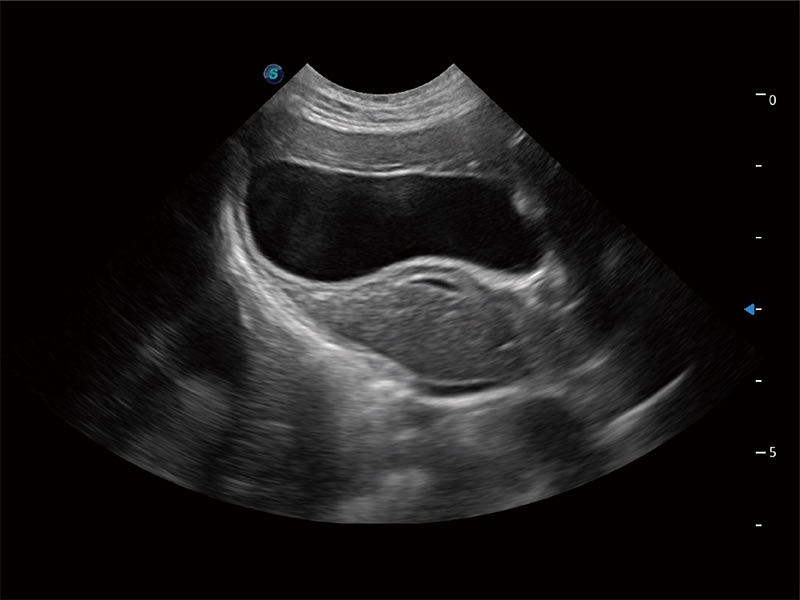

ProPet 80 配备了丰富的心脏探头群、先进的成像技术和专业的心脏测量工具,可帮助动物医生为不同体型和生理结构的动物提供心脏和心肌功能的全面评估。

能够增加心肌组织与血流之间的区别。对于心脏扫查困难的动物,可提供更好的心内膜边界的显示。

能够基于左心室壁追踪和辛普森法,自动计算射血分数,支持多个可移动点描迹,与手动测量相比,极大节省了动物医生的时间和精力。